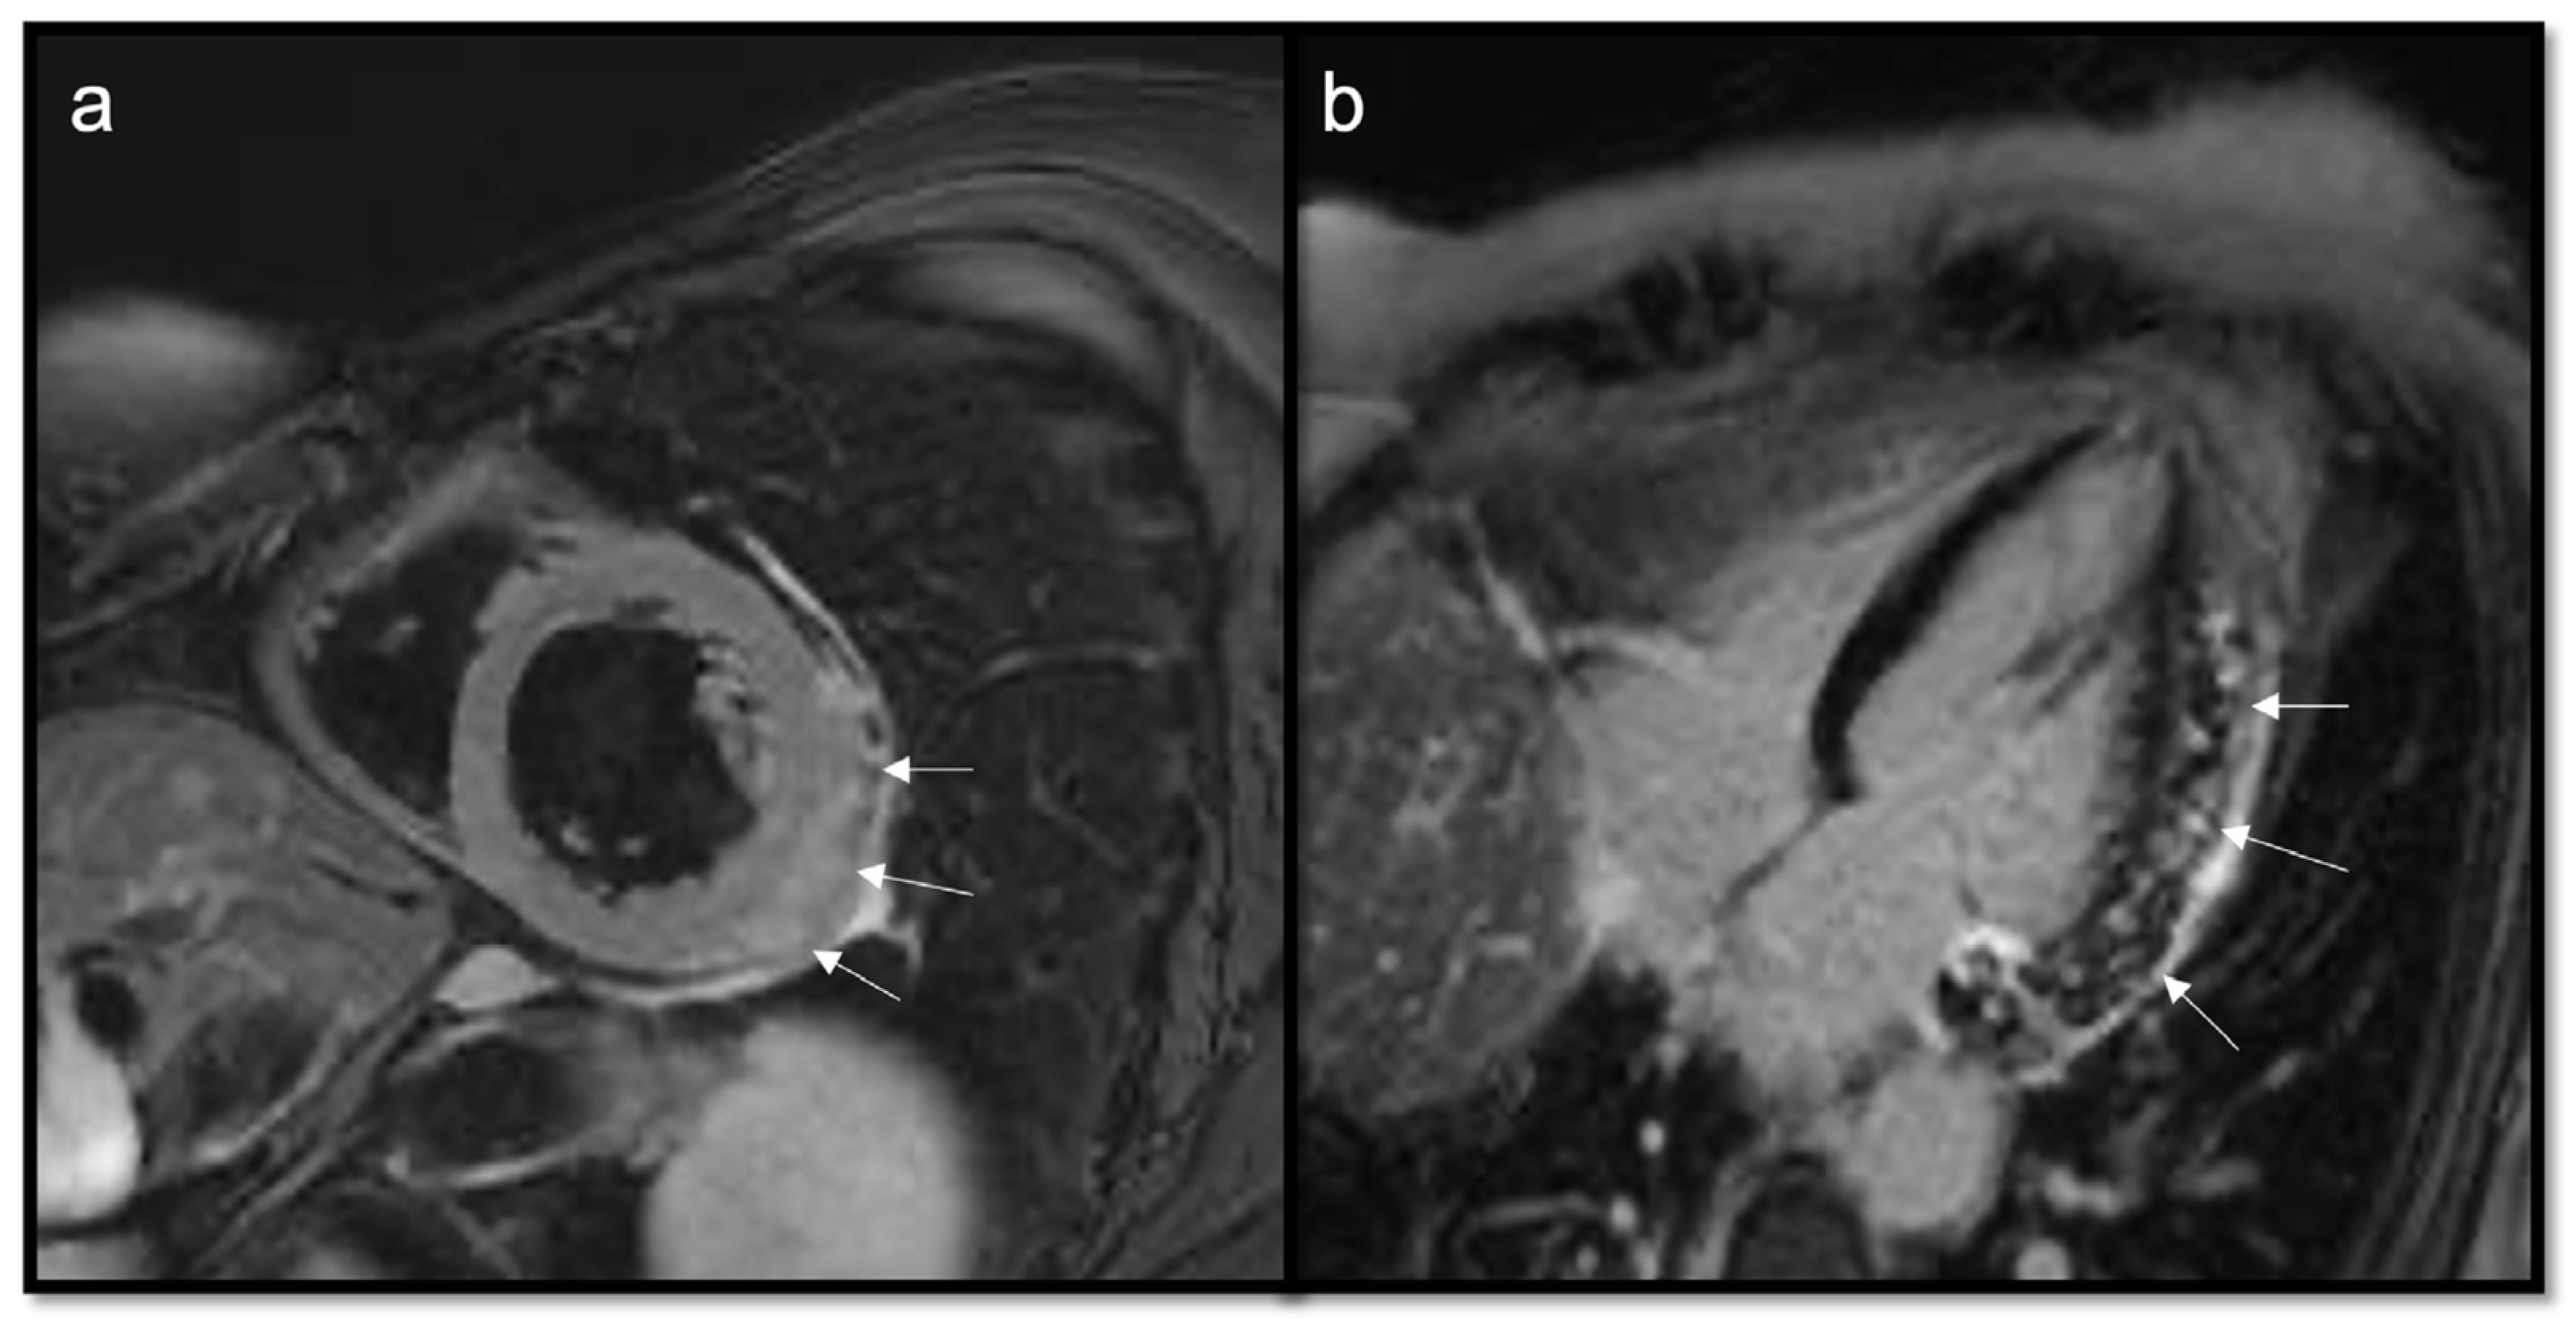

Figure 7.

Typical myxoma (arrow) appears as a well-defined, smooth, oval, or lobular lesion, has an intermediate signal in T1w (a), heterogeneous hyperintensity in T2w and T2w Fat Sat (b,c), linked to the high presence of water in the myxoid stroma. It shows limited enhancement on first-pass perfusion sequences (d) and progressive heterogeneous enhancement on late gadolinium enhancement (LGE) sequences due to its fibrous content (e,f). Some cases may show hyperintensity on T1w images due to hemorrhagic foci. Cine imaging is of particular value in this case as these lesions can be highly mobile and prolapse through the atrioventricular valves during diastole, causing temporary obstruction to blood flow.